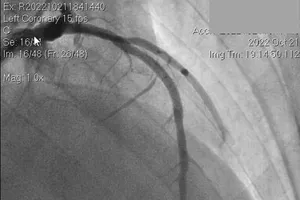

Cụ thể, năm 2019, BV ứng dụng phần mềm RAPID trong chẩn đoán và điều trị bệnh nhân đột quỵ. BV cũng là đơn vị đầu tiên trên cả nước đã triển khai phần mềm này để hỗ trợ thực hiện can thiệp nội mạch lấy huyết khối bằng dụng cụ cơ học.

Nhờ đó, khoảng 50% bệnh nhân đột quỵ đến BV trong khoảng thời gian từ 6-24 giờ được can thiệp nội mạch. Đến nay, BV đã có 2.200 ca đột quỵ được hệ thống này rà soát, 48% người bệnh được can thiệp thành công có thể vận động bình thường.